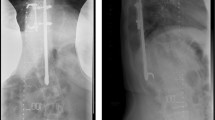

This was a single centre, cross-sectional retrospective study. Fourteen consecutive patients (two boys and 12 girls) with early-onset scoliosis attending the Spine Deformity Clinic with an average age of 10.4 years (5–15 years) at the time of surgery and treated with magnetically controlled growing rod (MCGR) system during the period from 2010 to 2017 with a minimum postoperative follow-up of 24 months were recruited in the study group. The average time between the index surgery and the time the blood was drawn was 43.7 months (28–79). The subjects comprised of six patients with idiopathic scoliosis, two patients with neuromuscular scoliosis and six patients with syndromic scoliosis (Table 1). Of the 14 patients, patients with Cerebral palsy and those with Prader Wili syndrome, Andersen Tawil syndrome and Rett syndrome were unable to ambulate independently due to their primary syndromic condition. The remaining nine patients were independent ambulators. Twelve patients were implanted with the first generation MCGR while two received the newer generation rod. All patients underwent a dual rod construct. A total number of 111 screws were used at the anchor points with 7.9 screws per construct (range 6–11) (Table 2).